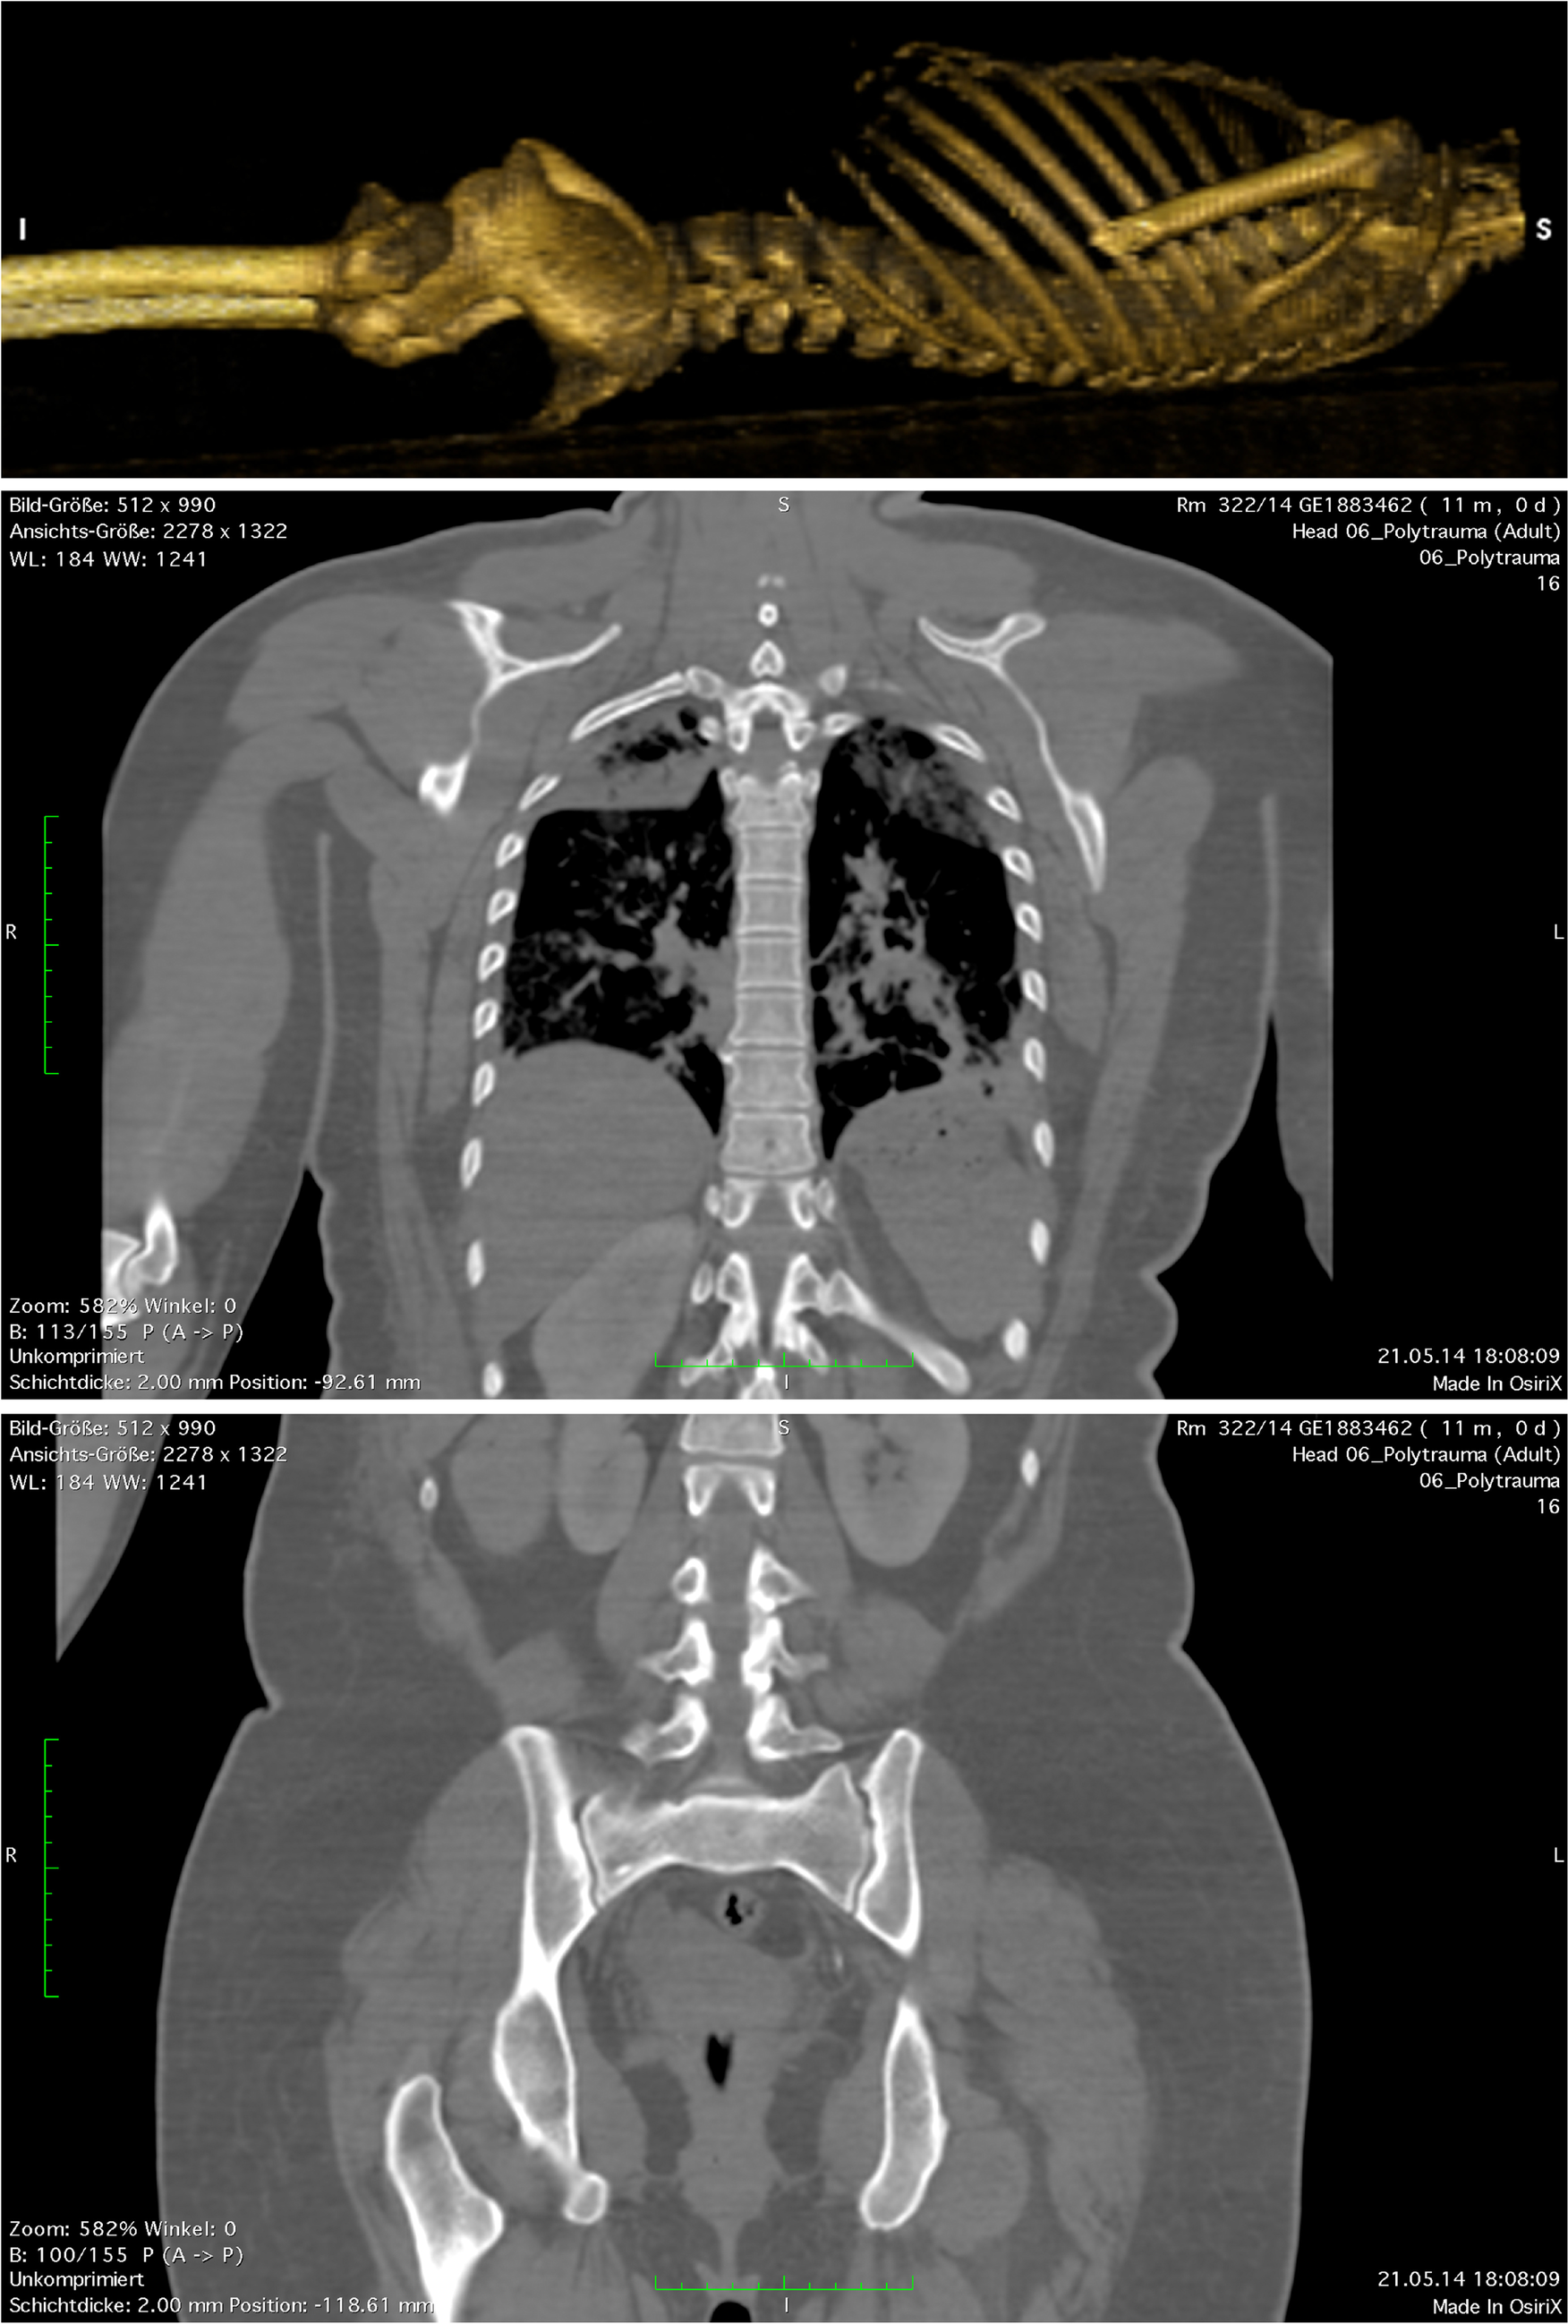

On the basis of the wound trajectory identified in 3D-reconstructed CT data, in which the bullet track was determined as a straight line from entry to exit wound (measured distance: 36 cm), the expectation had been that the bullet would have entered the thoracic and the abdominal cavities and that it would have perforated the right lung and the liver (Fig. 5).

Fig. 5

3D reconstructed CT datasets in volume-rendering mode, depicting the virtual wound trajectory and measurement of the straight connection between entry and exit wounds. After aligning the torso in the frontal plane, the cutting tool in OsiriX was used to cut the image along the bullet track. The parts of the torso that faced towards the lower left were eliminated. The ensuing cross section was then aligned in the frontal plane, and the exit and entry wounds were connected, using a measuring tool. The approximately 36-cm-long bullet trajectory can be seen to pass through the thoracic and the abdominal cavities

The wound track left by the third, tangential, bullet was, however, so unusual that we believe it merits reporting. In the trajectory analysis of this wound from 3D reconstructed CT data sets, the linear distance measured between entry and exit wounds was approximately 36 cm. In this straight trajectory through the body, the bullet would have had to traverse the thoracic and abdominal cavities; however, the actual wound channel was not found to pass through either of these cavities. The bullet had, instead, followed an approximately 40-cm-long, nonlinear trajectory though the subcutaneous adipose tissue. Contact with bone could be excluded as a reason for bullet deflection. The contusion in the medial lobe of the right lung and the hemorrhage in the adipose tissue around the right kidney were, therefore, likely caused by expansion of the temporary cavity around the wound channel.